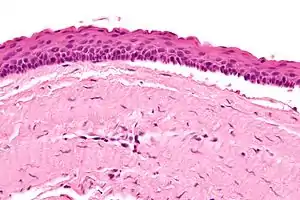

Micrograph of an odontogenic keratocyst. H&E stain.

Odontogenic keratocysts have a diagnostic histological appearance. Under the microscope, OKCs vaguely resemble keratinized squamous epithelium;[13] however, they lack rete ridges and often have an artifactual separation from their basement membrane.[2]

The fibrous wall of the cyst is usually thin and uninflamed. The epithelial lining is thin with even thickness and parakeratinised with columnar cells in the basal layer which have focal reverse polarisation (nuclei are on the opposite pole of the cell).[11] The basal cells are an indication of the odontogenic origin as they resemble pre-ameloblasts. The epithelium can separate from the wall, resulting in islands of epithelium. These can go on to form 'satellite' or 'daughter' cysts, leading to an overall multilocular cyst.[9] Presence of daughter cysts is particularly seen in those with NBCCS.[11] Inflamed cysts show hyperplastic epithelium which is no longer characteristic of OKCs and can have resemblance to radicular cysts instead. Due to areas of focal inflammation, a larger biopsy is required for correct diagnosis of odontogenic keratocysts.[9]